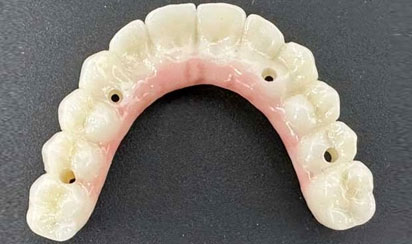

For your final teeth, you, the dentist, and our in-house lab technician will work together to design your perfect smile. While other offices still use acrylic denture teeth over titanium bars, we use zirconia for the best in appearance, durability, and resistance to staining. Upgrading to these materials usually costs significantly more at other offices. At Sumner Dental Group, they’re our standard.

We custom made all the teeth for each Patient.

No RETRO-FITTING is needed.

Custom-Made (OUR)

Match to Existing Natural Gum Tissue